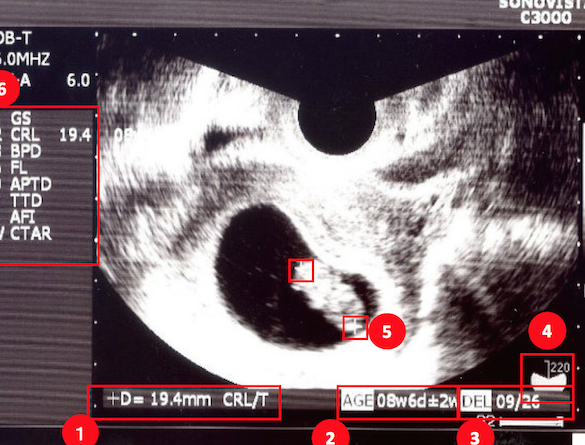

妊娠中の胎児診断

妊婦検診において、3Dエコーは胎児の成長や発育状態を確認するためによく使用されます。この技術によって、母体と胎児の健康状態を同時に監視できるため、安全な出産につながります。また、異常が見つかった場合には迅速な対応が可能です。